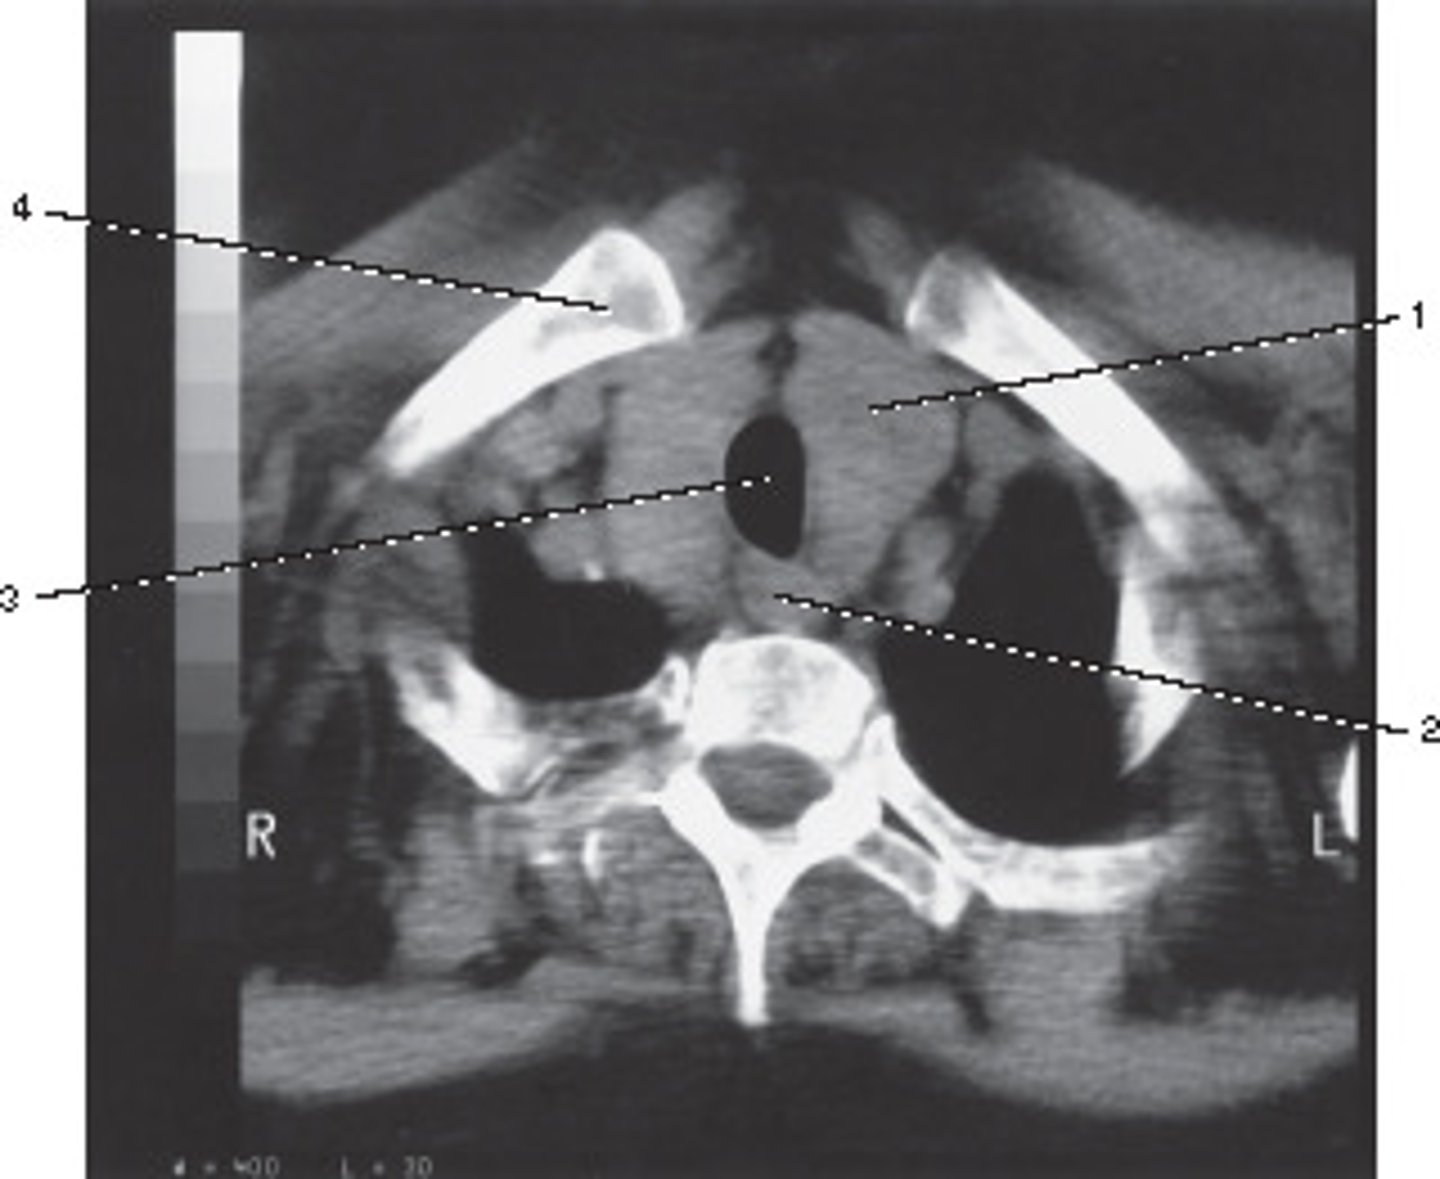

Enlarged Thyroid

What pathological process best describes the abnormal finding in this image?

<p>What pathological process best describes the abnormal finding in this image?</p>